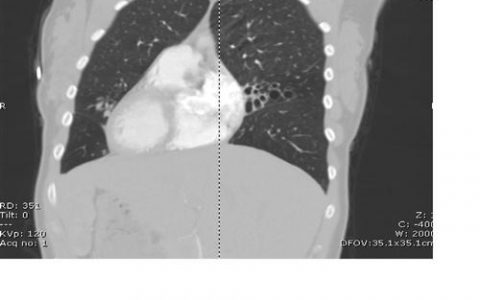

A 69-year-old woman with a history of asbestos exposure presented to the emergency department with a 3-year history of dyspnea on exertion. Physical examination showed signs of volume overload. A chest radiograph showed circumferential calcification of the pericardium and pleural effusions. Simultaneous left and right heart catheterization showed ventricular interdependence and discordance of the pressure tracings (right ventricular pressure, solid arrow; left ventricular pressure, dotted arrow). What is the diagnosis?

正确答案是缩窄性心包炎,这次是由石棉肺引起的。经胸超声心动图显示射血分数保留,舒张早期有间隔反弹,以及肝静脉呼气期舒张期逆转。左、右心导管同时示踪是缩窄性心包炎的特征性表现。吸气时右心室压力最高时,左心室压力最低;这种模式在到期时逆转。一个“平方根”符号(也称为倾角-平台模式;红线)表示舒张早期心室快速充盈,舒张晚期突然停止充盈。